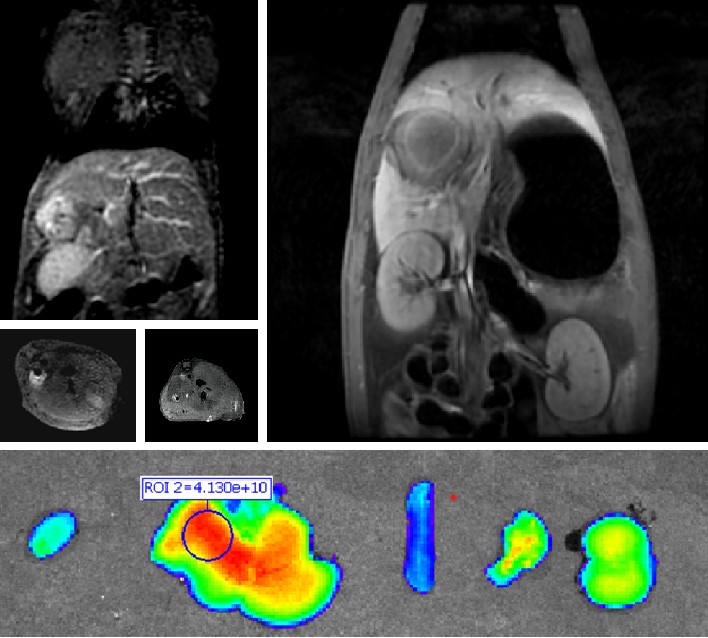

普利制藥自主研發(fā)雙模態(tài)造影劑PL002,首次提出通過整合磁共振技術(shù),彌補(bǔ)現(xiàn)有熒光染料假陽性率高、透射深度有限等的短板,進(jìn)而提升手術(shù)的精確性,降低手術(shù)過程中的風(fēng)險(xiǎn),是全球首個(gè)獲批臨床試驗(yàn)的熒光/磁共振雙模態(tài)造影劑,目前也已經(jīng)獲得美國(guó)FDA臨床試驗(yàn)批件。